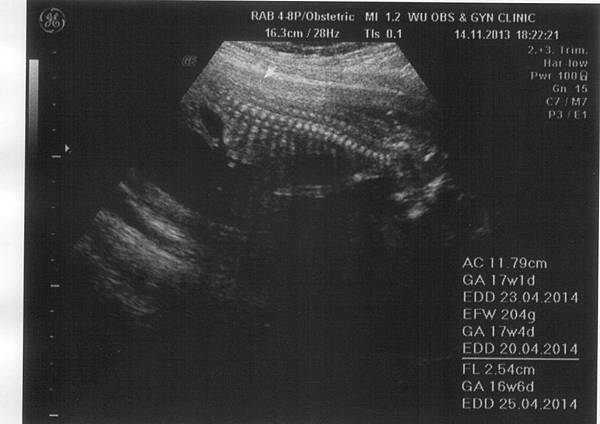

• 9月 11 週三 201311:59

1234591_10201768014351894_723686032_n.jpg4w4d.jpg8w2d-1.jpg8w2d-2.jpg

(繼續閱讀...)